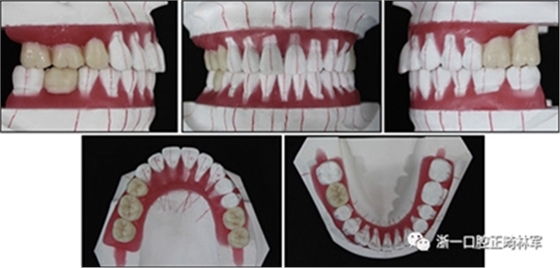

口腔內由于牙周炎,她的上頜右側第一和第二前磨牙,上頜右側第一和第二磨牙,上頜左側第一和第二磨牙以及下頜右側第一磨牙缺失。牙周探查顯示在磨牙區(qū)域和下頜骨左側側切牙區(qū)有深的牙周袋,還存在出血(表I)。上頜骨和下頜骨前牙擁擠,左側側切牙存在反合,下頜左側側切牙發(fā)過度萌出。覆蓋是5毫米,上頜切牙是唇傾的。在上頜弓中,尖牙和前磨牙是近中傾斜,右側尖牙過度萌出。而且,下頜右側第二磨牙向近中傾斜。尖牙處于I類關系,但無法評估磨牙關系(圖1和2)。

圖2. 治療前牙齒石膏模型